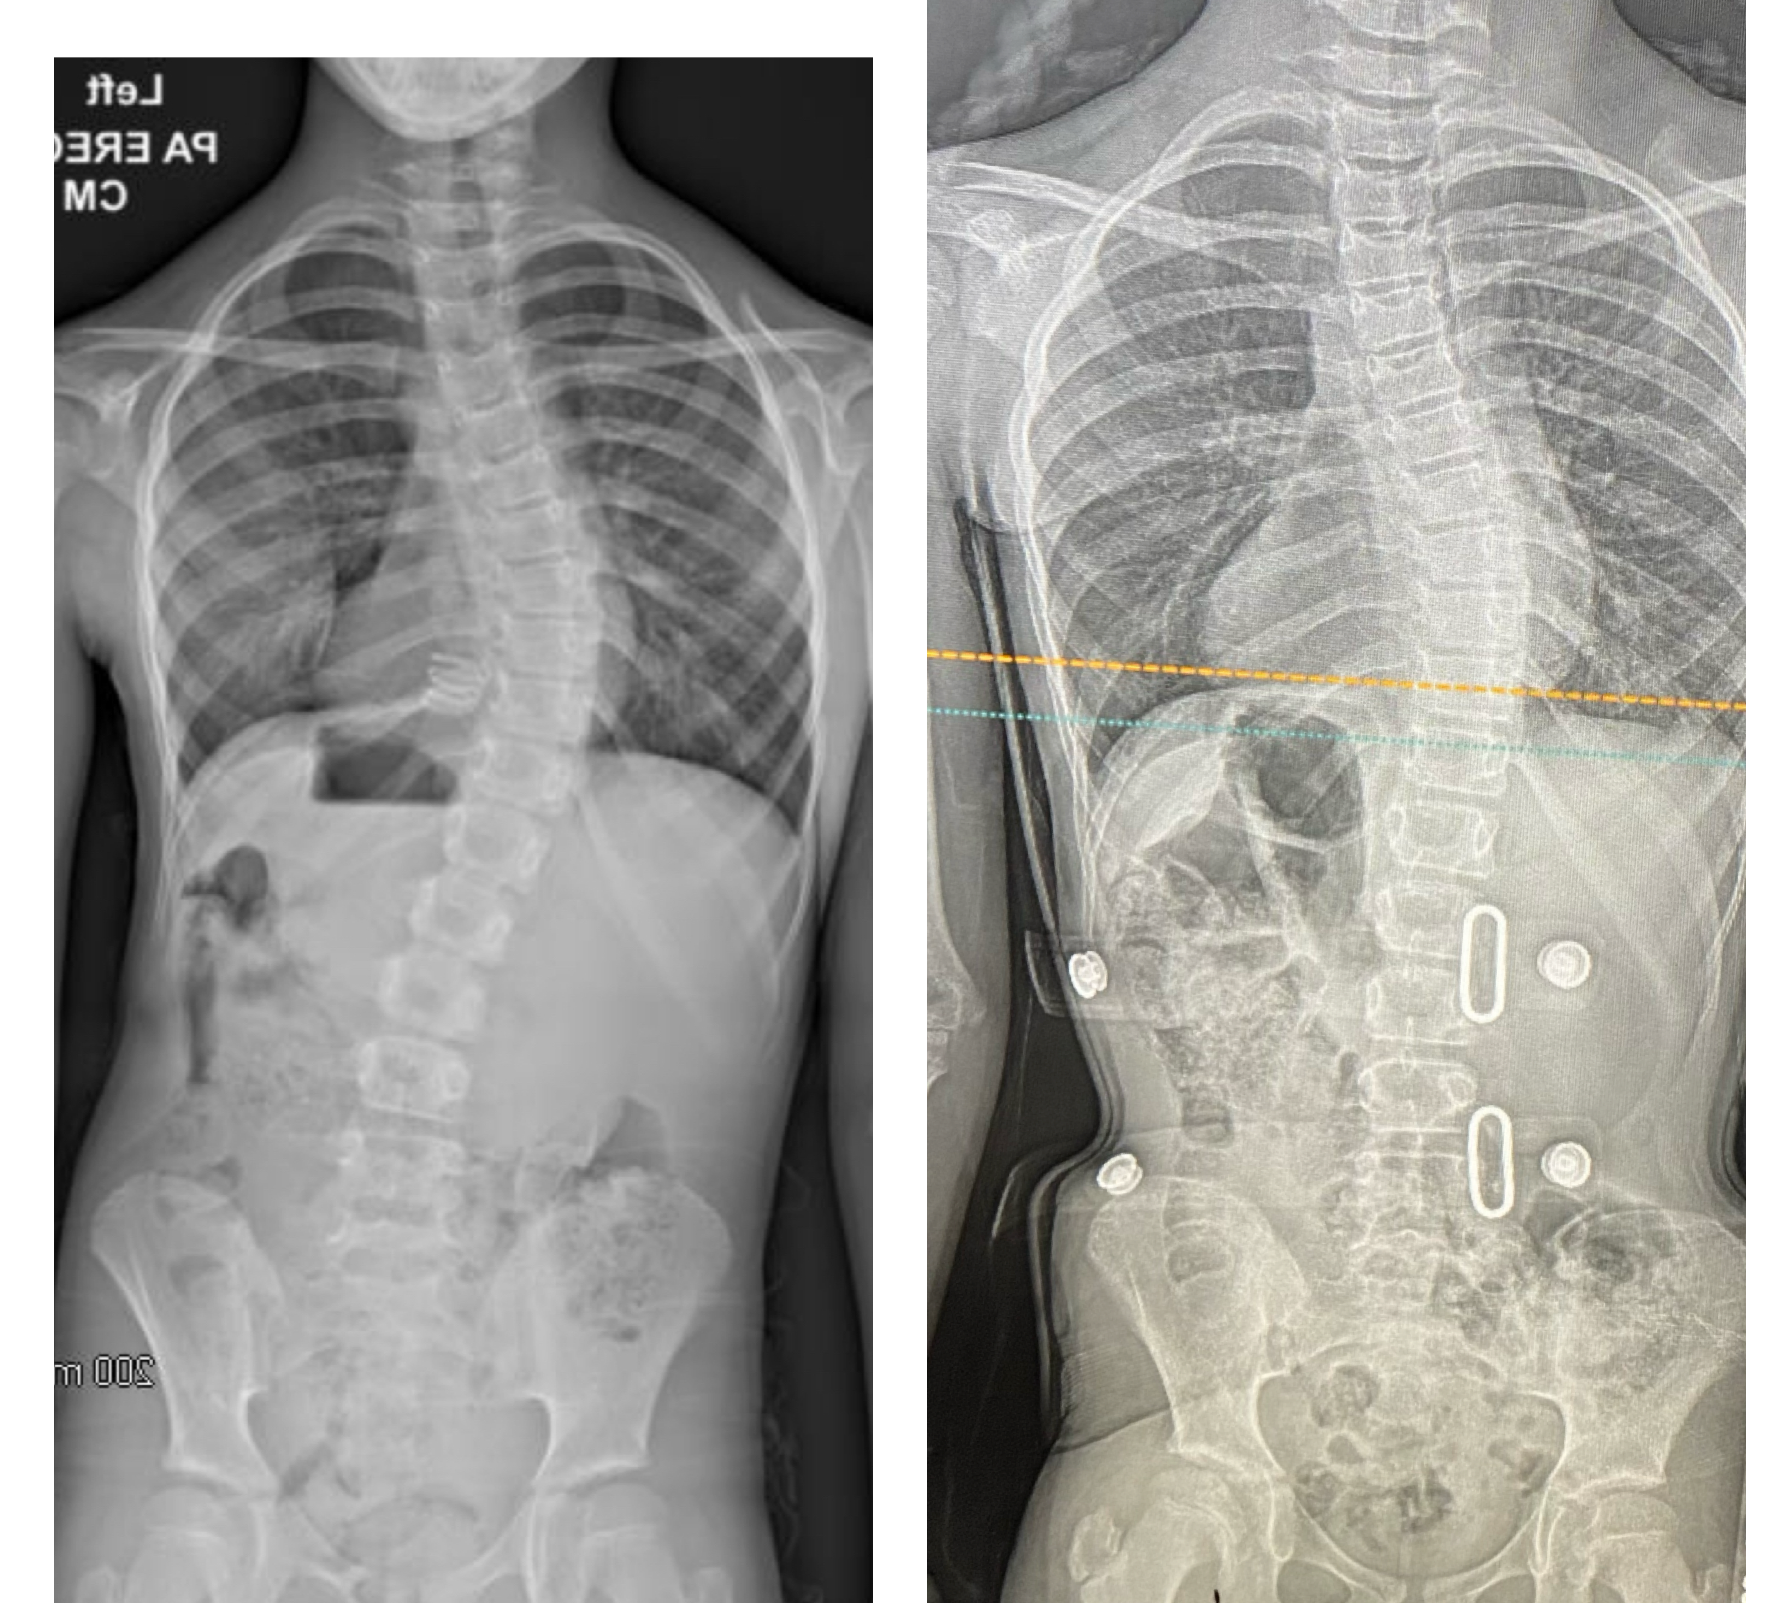

Първата ни снимка с корсета беше на 6 декември след 5 седмици и половина носене. Изпратиха ни за лека поправка на корсета и днес я направиха. Повдигнаха рамото още и увеличиха натиска от дясната ѝ страна. Март месец ни предстои нова снимка с него.

Колко градуса са ъглите на изкривяване преди корсета?

Браво! Моето дете за месец и половина намали градусите от 26 на 18 само с упражнения.

След това сложи корсет и е на снимка на 18.01. Да видим.